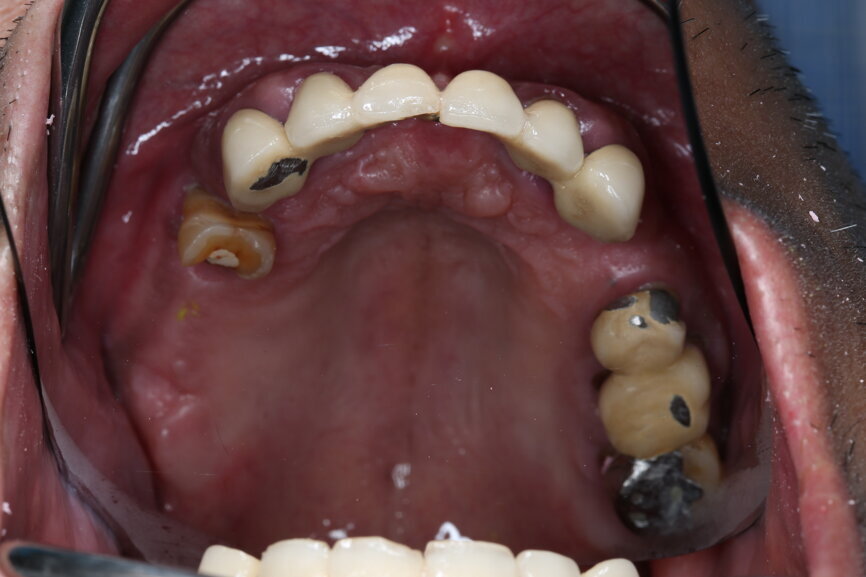

A 51-year-old male patient who was a smoker (< 10 cigarettes per day) and in good general health presented to the clinic with missing molars in the second and fourth quadrants, Grade III mobility of teeth #24 and 17, decayed roots and gingival inflammation, and without abscess or sinusitis of tooth #16. The anterior zone showed  different extents of recession, bone resorption and deep periodontal pockets around teeth #12 and 22, which led to the patient complaining about an aesthetically unsatisfying restoration (Figs. 1 & 2).

On the day of surgery, we prepared for the surgical protocol provided by the implant planning software, which guided us on the drilling sequence and the use of the appropriate instruments for the implant bed preparation (Figs. 30a & b). After the fixation pins had been allocated, teeth #17, 16, 15, 13, 12, 22, 23 and 24 were atraumatically extracted and alveolectomy was performed using a bone reduction guide (Figs. 31–36). Four implants (Straumann BLX; regular base; diameter: 4.5 mm; length: 12.0 mm) were placed, two straight implants in the anterior and two titled implants in the posterior. All the implants were stabilised to a torque of 50 Ncm (Figs. 37–43), and the SRAs were placed on top. The SRAs on the posterior implants had an angulation of 30° (diameter: 4.6 mm; gingival height: 3.5 mm) and on the anterior implants an angulation of 17° (diameter: 4.6 mm; gingival height: 3.5 mm; Figs. 44 & 45).